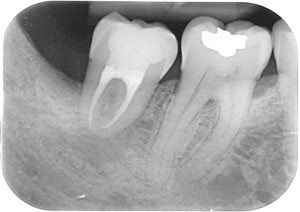

Second molar extraction pros and cons. 2nd molar extraction - pros and cons. 3rd molars x4 extracted late teens. 2nd molar upper right had a very large cavity - sensitive - 4 years ago.

The dentist I saw then did a filling with a topical antibiotic or somethign like that - and I remember him telling me the tooth was not worth a. 2nd molar extraction pros and cons Sep 16 2021 I read that many patients are OK with their second molars removed. My understanding is that the loss of chewing abilities there is very minor.

Aside from a couple of fillings her two upper second molars 2 15 were bad enough that 2 needs to be pulled and 15 could either be pulled or have a root canal done followed by a crown the. Whether or not a second molar should be replaced after its removal is debatable. To assess the evidence and discuss the pros and cons of replacing a missing second molar with a dental implant restoration the authors searched the literature for articles that evaluated the following factors.

Extracting a second molar tooth causes the least complications. A second molar does not have a tooth behind it that will drift after the extraction. We recommend that you have another discussion with your dentist about the pros and cons of keeping the tooth or removing it.